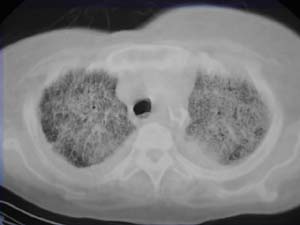

以下是引用liaizhi在2007-7-6 0:05:00的发言:[br]双肺纹理膜糊,沿纹理走行有班点状高密度影。考虑心衰并肺水肿。

以下是引用andymaomao在2007-7-5 22:23:00的发言:[br]双上肺明显,考虑心衰并肺水肿,双侧胸腔少量积液!另不除外肺泡蛋白沉着症及肺泡ca可能。[br]联想机制——心脏病(代偿期)--肺部淤血--后可能并感染致病情加重--抗炎治疗好转,但肺淤血严重,心功能失代偿--心衰而死亡!

以下是引用拾荒者在2007-7-6 13:06:00的发言:[br]支持:心衰,肺水肿及ards